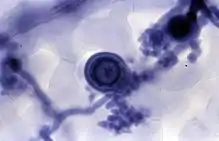

It may be used to observe fungal hyphae[6] and stramenopiles.